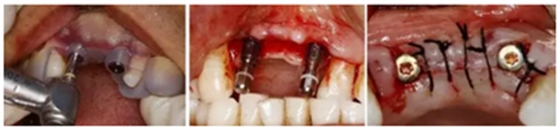

(1)拔牙后PRF復(fù)合GBR技術(shù)行位點(diǎn)保存

2.png

3.png